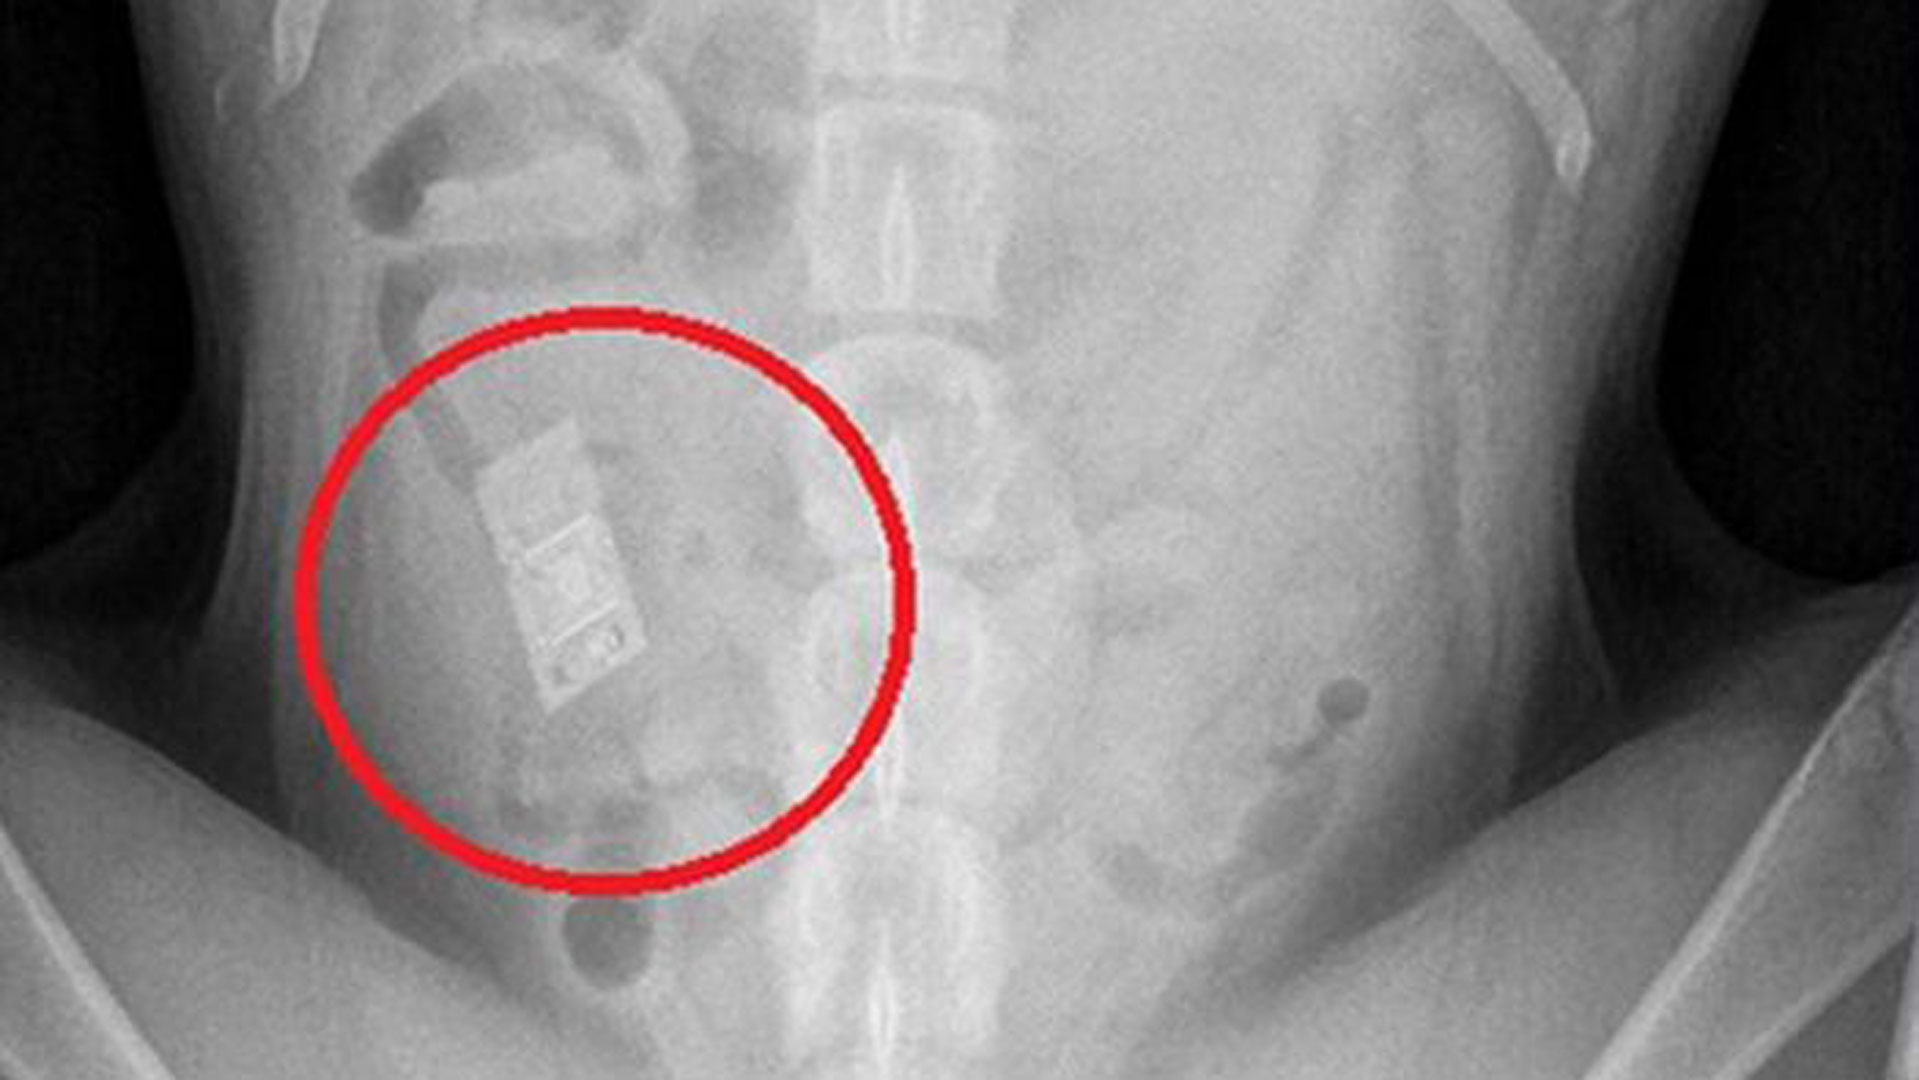

在吃下去后,这些异物可能会自行流到了肠道,在我们还没发觉的时候,它们就自行排泄出去了。

但这些异物如果挂在了它们的胃肠道,就非常危险了,必须尽快手术取出。

如果宠物们有明显的症状还好,我们就可以直接带它去宠物医院,精密检查定位异物位置。

这样,不能第一时间确诊并治疗,病情很可能会严重到,异物刺穿胃壁、肝脏、甚至造成肠道堵塞,内脏坏死。